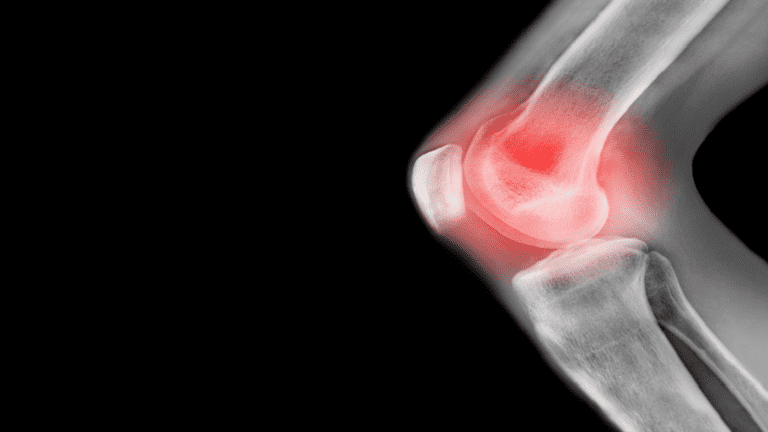

خبرني - التهاب المفاصل هو حالة شائعة تسبب ألما وأوجاعا في المفاصل، ولسوء الحظ، يمكن أن يكون مؤلما جدا للبعض، وقد يؤثر على الأشخاص من جميع الأعمار.

وتختلف أعراض التهاب المفاصل حسب النوع الذي يعاني منه المريض (مثل هشاشة العظام أو التهاب المفاصل الروماتويدي). وبالإضافة إلى التسبب في الألم والتصلب، يمكن أن يُحدث الالتهاب ضررا دائما للمفاصل، وهو ما يتطلب بدء العلاج مبكرا للمساعدة في تقليل الضرر.

وتنص مؤسسة التهاب المفاصل على أن: "تصلب الصباح الذي يستمر لأكثر من ساعة هو سبب وجيه للاشتباه في الإصابة بالتهاب المفاصل. والعلامتان الرئيسيتان الأخريان للمرض هما التورم وصعوبة تحريك المفصل".

وإذا كنت مصابا بالتهاب المفاصل، فمن المرجح أن تشعر مفاصلك بالتيبس ويصعب تحريكها، وقد تجد أيضا أن المنطقة المحيطة بالمفاصل قد تشعر بالدفء أو تبدو حمراء أو منتفخة.